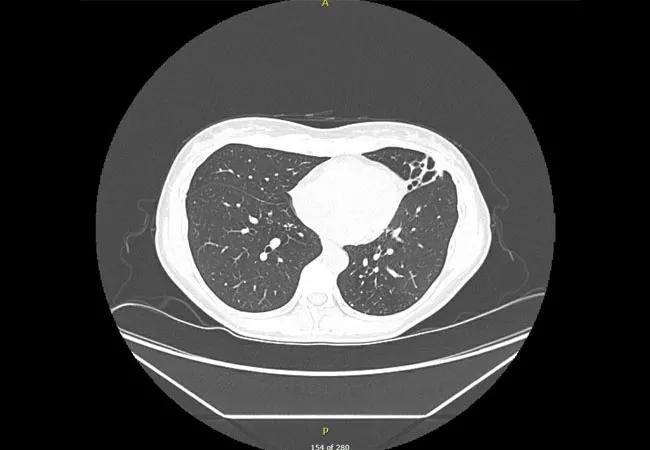

After six months, due to side effects and still no microbiological response, all medications again were stopped and the patient was referred to Cleveland Clinic’s Nontuberculous Mycobacteria (NTM) Center for refractory, macrolide-resistant MAC infection. At that time, a CT scan revealed increased left-lung-predominant, small, clustered nodules and lingular-predominant bronchiectasis, most likely due to worsening infection.

CT scan showing increased left-lung-predominant, small, clustered nodules and lingular-predominant bronchiectasis.